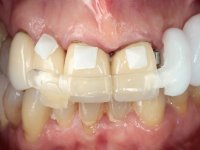

Paciente do sexo feminino, com 69 anos, não fumadora. Apresenta uma prótese combinada no maxilar superior. A porção fixa corresponde a uma ponte metalo-cerâmica de 4 elementos com os dentes 1.3/1.1 e 2.1 como pilares e o dente 1.2 como pôntico. A porção amovível corresponde a uma prótese esquelética de 5 elementos. A retenção da prótese esquelética é feita por um gancho no dente 1.4 e um “attachment tipo t” colocado no dente 2.1.

A reabilitação proposta, consistia na colocação de uma ponte metalo-cerâmica implanto-suportada no 2º quadrante, evitando-se a prótese esquelética. Após a realização do estudo imagiológico, seria decidido definitivamente, o número e localização dos implantes a colocar. A paciente não mostrou interesse na substituição da ponte metalo-cerâmica antero-superior.

O estudo imagiológico para a colocação dos implantes, começou com a realização em laboratório de uma guia com dentes em sulfato de bário. Esta guia foi colocada em boca conjuntamente com marcas de referência coladas aos dentes, também em sulfato de bário. A guia foi estabilizada com cera mole. A TAC foi realizada com estas referências colocadas em boca. Após a realização da TAC foi feita uma impressão de arrasto em silicone. Esta impressão foi vazada a gesso em laboratório e posteriormente digitalizada. A digitalização do modelo com as referências foi sobreposta á imagem da TAC, permitindo uma planificação apurada na colocação dos implantes. Na planificação foi decidido colocar 2 implantes no local dos dentes 2.3 e 2.4 evitando-se a zona do 2.2 com pouco osso e o seio maxilar. Este estudo deu origem a uma guia cirúrgica que orientou a colocação dos implantes. Durante o período de osteo-integração a paciente utilizou a prótese removível rebasada com acondicionador de tecidos. A guia cirúrgica mostrou-se também útil na exposição dos implantes mostrando a sua localização precisa e orientando a incisão. A impressão definitiva foi realizada utilizando a técnica de moldeira aberta após eliminação do attachment. No laboratório foi confeccionada uma ponte metalo-cerâmica de 3 elementos com o elemento 2.2 em suspensão. A ponte após verificação e aprovação foi cimentada. A reabilitação apesar de pouco extensa (sem o elemento 2.6) mostrou-se capaz estetica e funcionalmente.